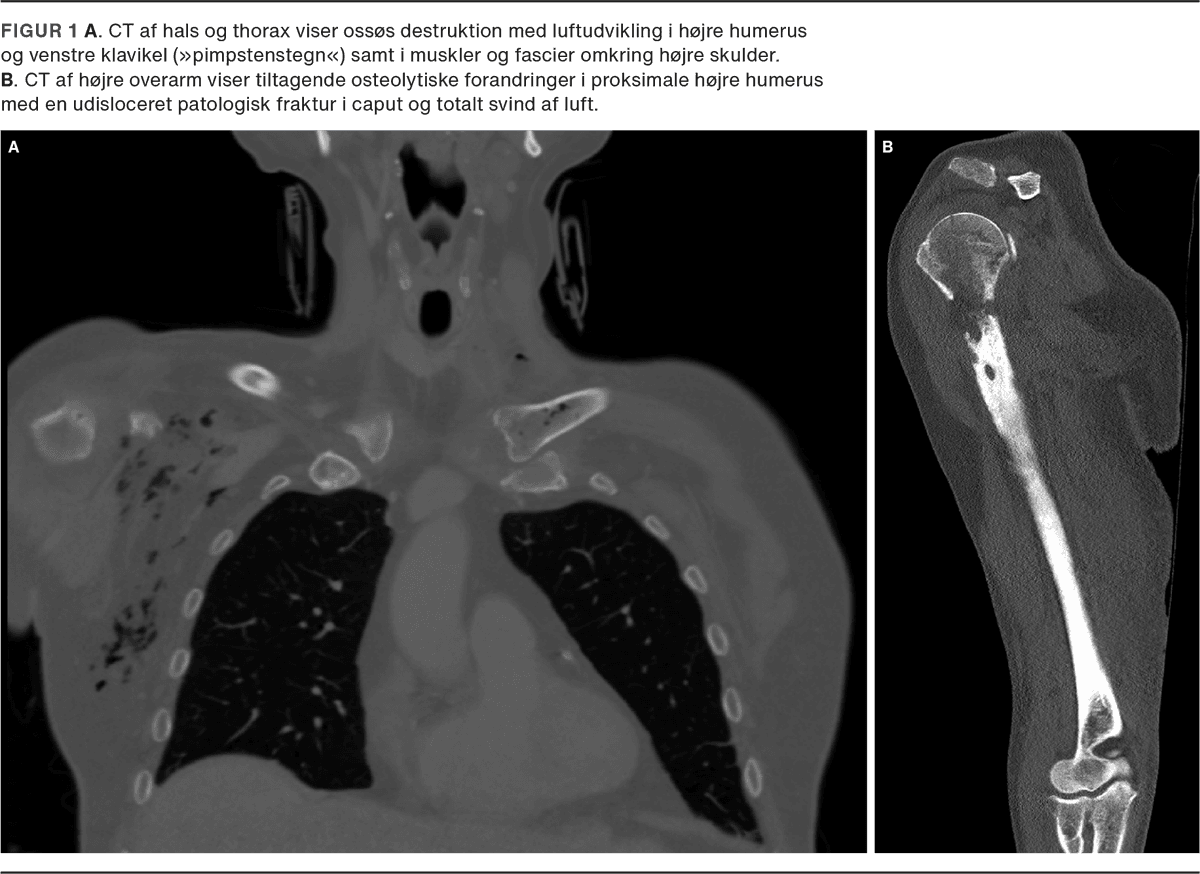

Med tiltagende smerter og nytilkommen hævelse af højre overekstremitet viste en fornyet CT en nytilkommen ossøs destruktion med luftudvikling i højre humerus og omkringliggende muskler og fascier samt luftudvikling i venstre mediale klavikelende (Figur 1A). Disse fund var forenelige med EO.

Efter tre måneder uden antibiotika blev patienten genindlagt med recidiv af osteomyelitis (Figur 1B) og udviklede en absces i højre overarm. Dyrkninger af materiale fra UL-vejledt drænage viste K. pneumoniae med uændret resistensmønster. Patienten fik herefter i.v. antibiotika i tre måneder med god effekt.